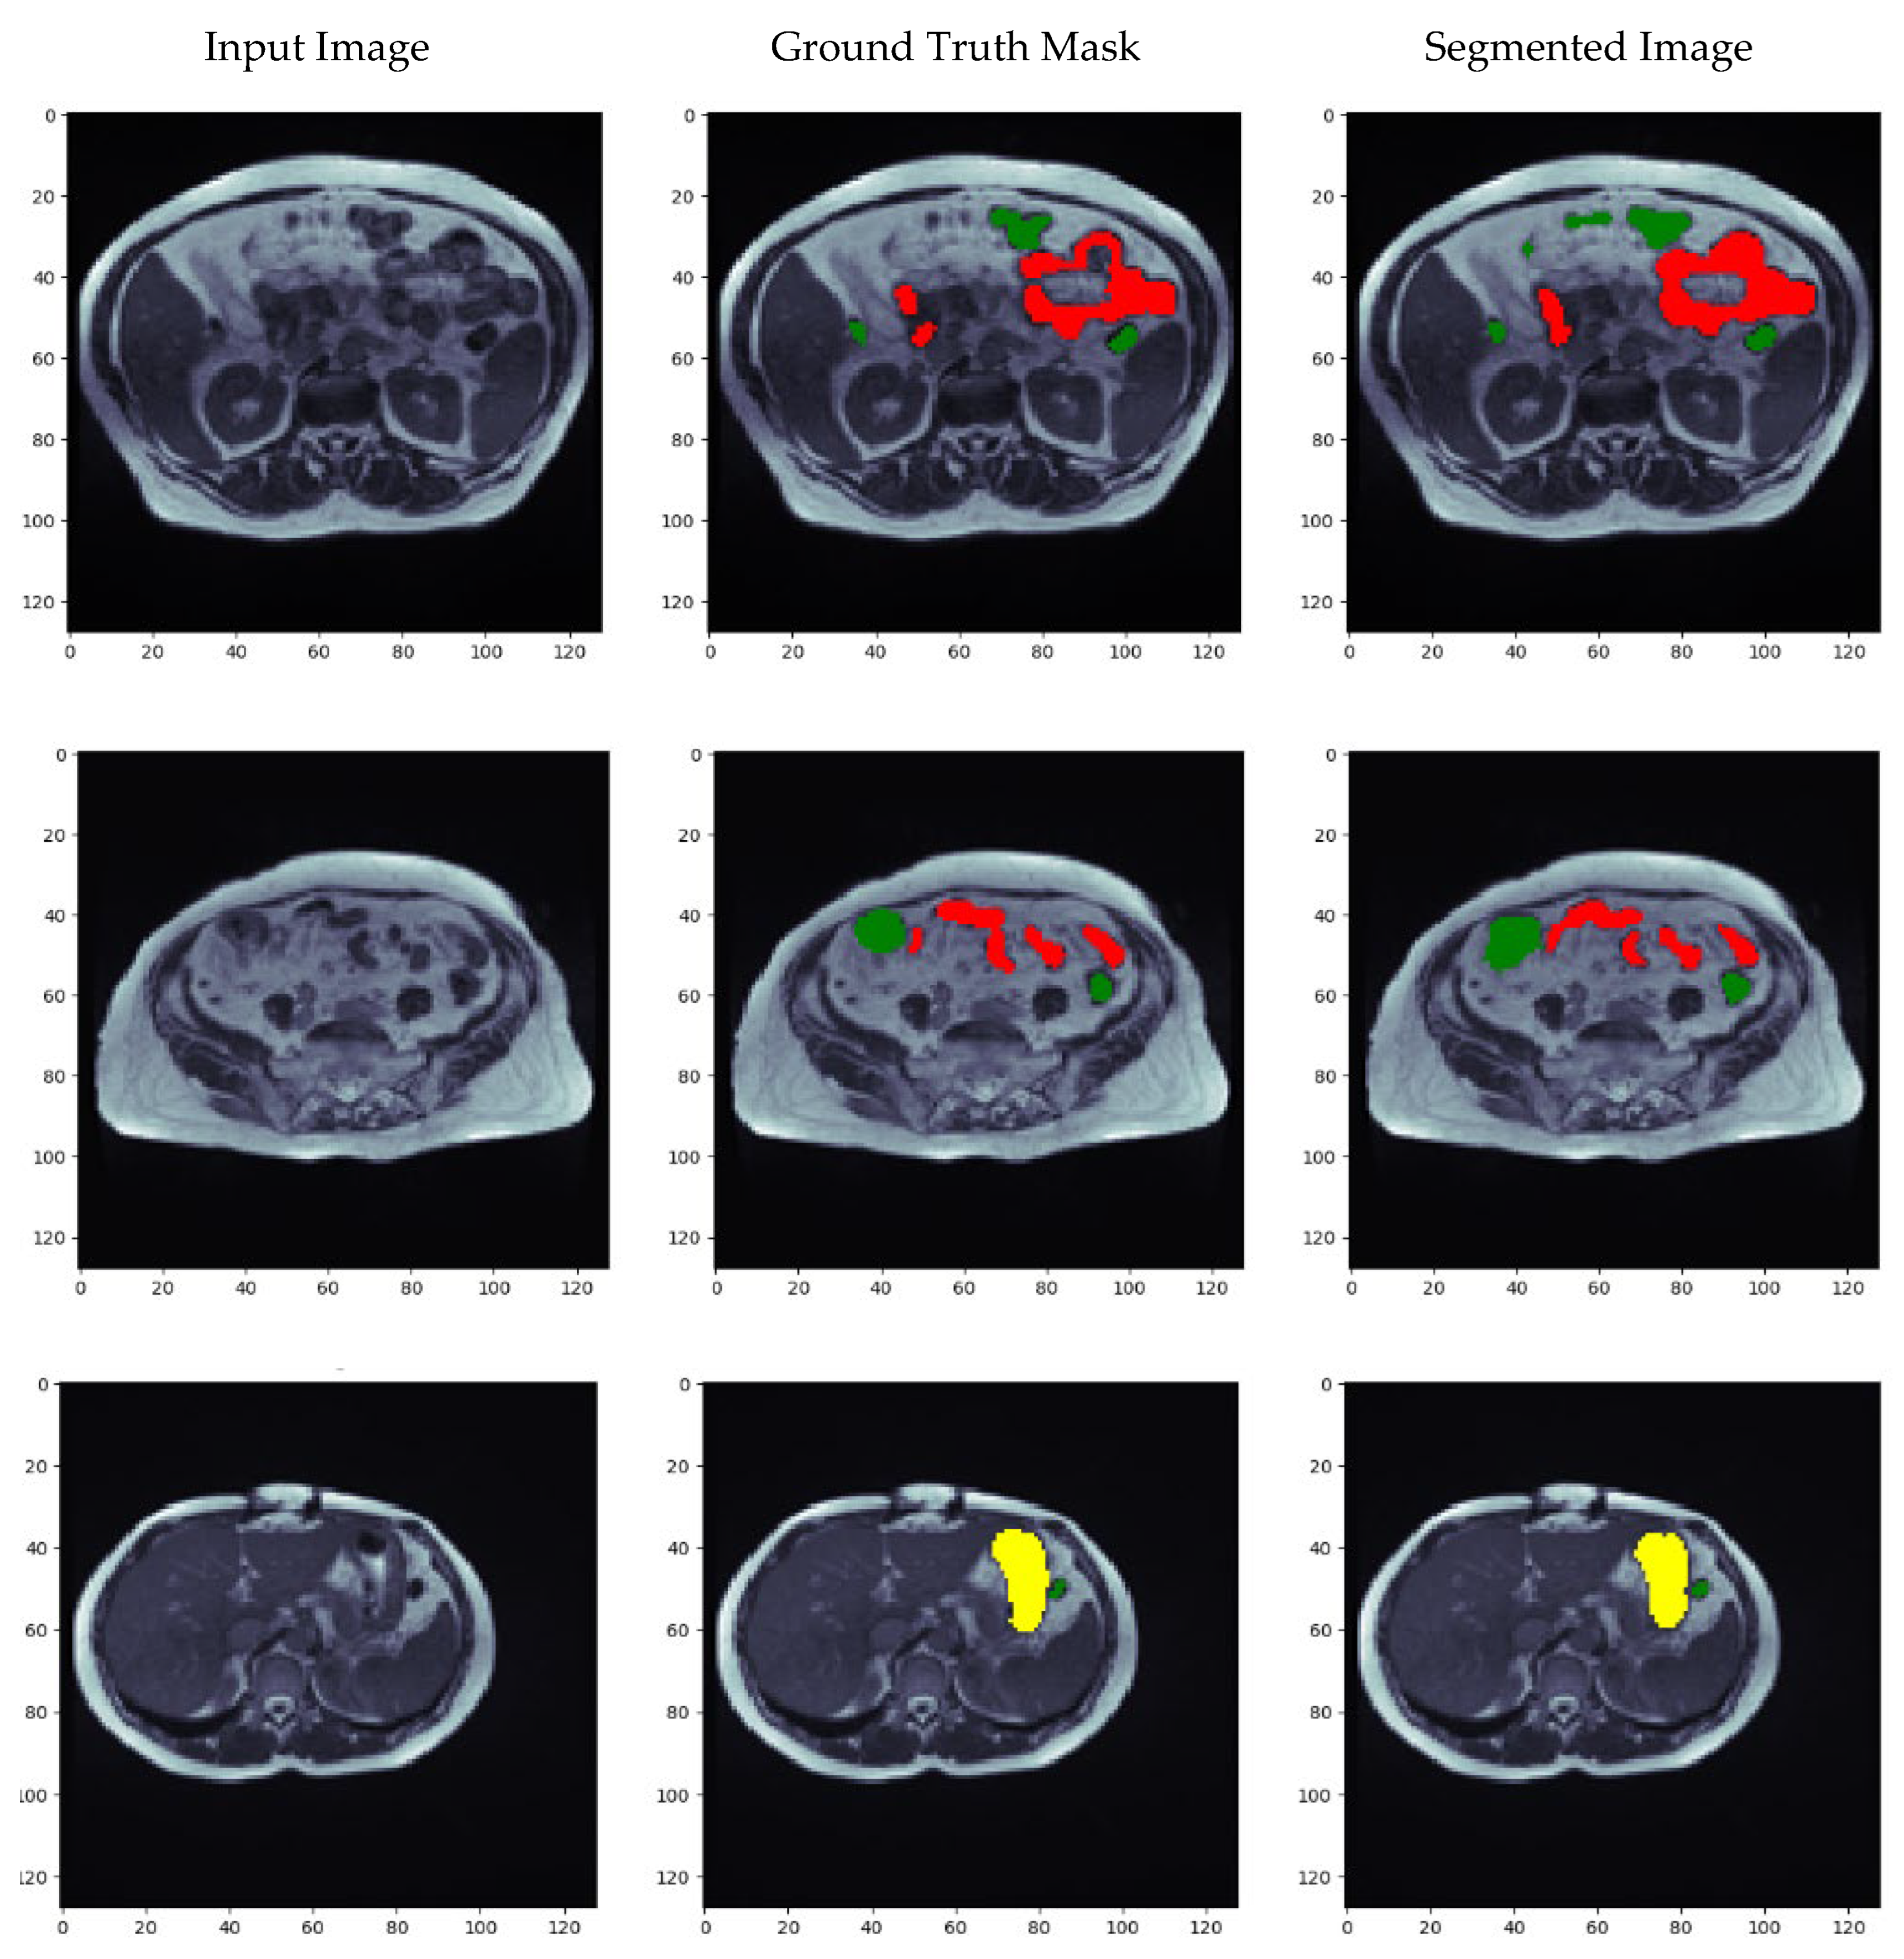

5.7. Visualization of Results for the Best Optimized Model